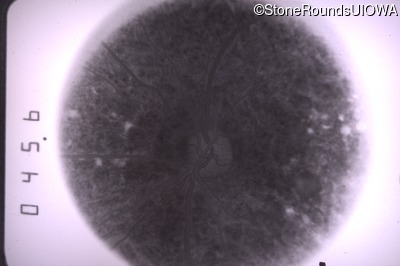

Goldmann Visual Field - Left - 20/20 sc

Exemplar